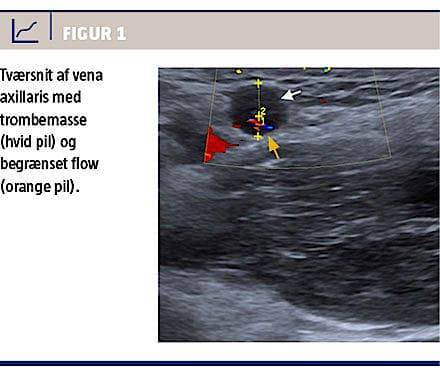

En akut UL-skanning af venstre arm med farve-Doppler viste massiv trombedannelse fra overgangen mellem vena brachialis og vena axillaris centralt til indgangen til vena brachiocephalica samt en PM-elektrode i tromben. På Figur 1 ses trombemasse i vena axillaris.

D-dimer på andendagen var fortsat normal, 0,4 mg/l. Patienten blev sat i behandling med warfarin og tinzaparin 175 IE/kg, som blev givet en gang dagligt, indtil international normaliseringsratio var i terapeutisk niveau.